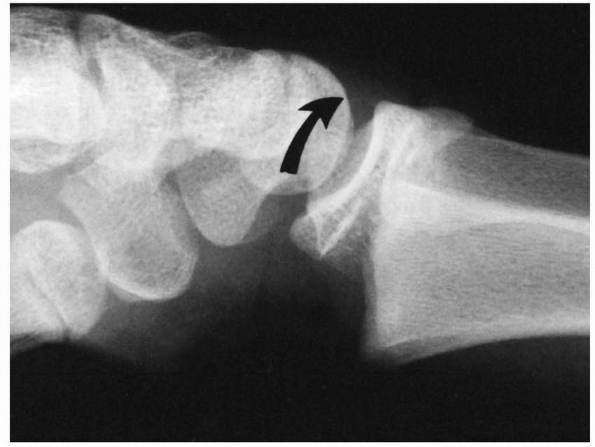

![]() |

FIGURE 9-8 Dorsally displaced physeal fracture (type A). The distal epiphysis with a small metaphyseal fragment is displaced dorsally (curved arrow) in relation to the proximal metaphyseal fragment.

FIGURE 9-9

Volarly displaced physeal fracture (type B). Distal epiphysis with a large volar metaphyseal fragment is displaced in a volar direction (curved arrow). (Reprinted from Wilkins KE, ed. Operative Management of Upper Extremity Fractures in Children. Rosemont, IL: American Academy of Orthopaedic Surgeons, 1994:21, with permission.) |